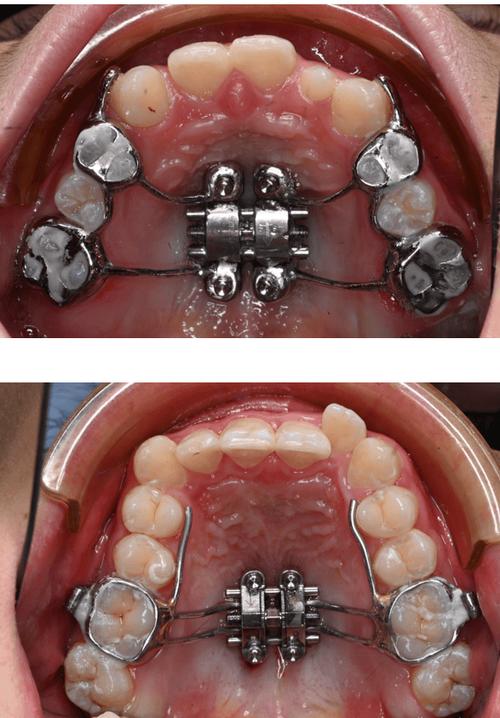

治疗前需通过口腔检查、X光片(曲面断层片、头颅侧位片)、模型分析等,明确牙齿位置、牙槽骨条件、牙弓宽度及面部软组织情况,通过测量(如牙弓宽度、前牙突度)和模拟设计,确定目标牙齿的移动量和移动方向,制定个性化的辅弓方案(如选择材质、弯制形态、确定加力周期)。

辅弓弯制

根据牙弓形态和移动需求,在模型或口内直接弯制辅弓,针对上颌前牙外展,需在尖牙之间弯制“外展曲”,曲的深度和角度需根据牙齿移动量计算(一般每侧外展1-2mm);若需扩大牙弓,可在后牙区放置螺旋弹簧,并预留压缩或伸展的空间,弯制时需注意弓丝的平滑度,避免尖锐刺激软组织。